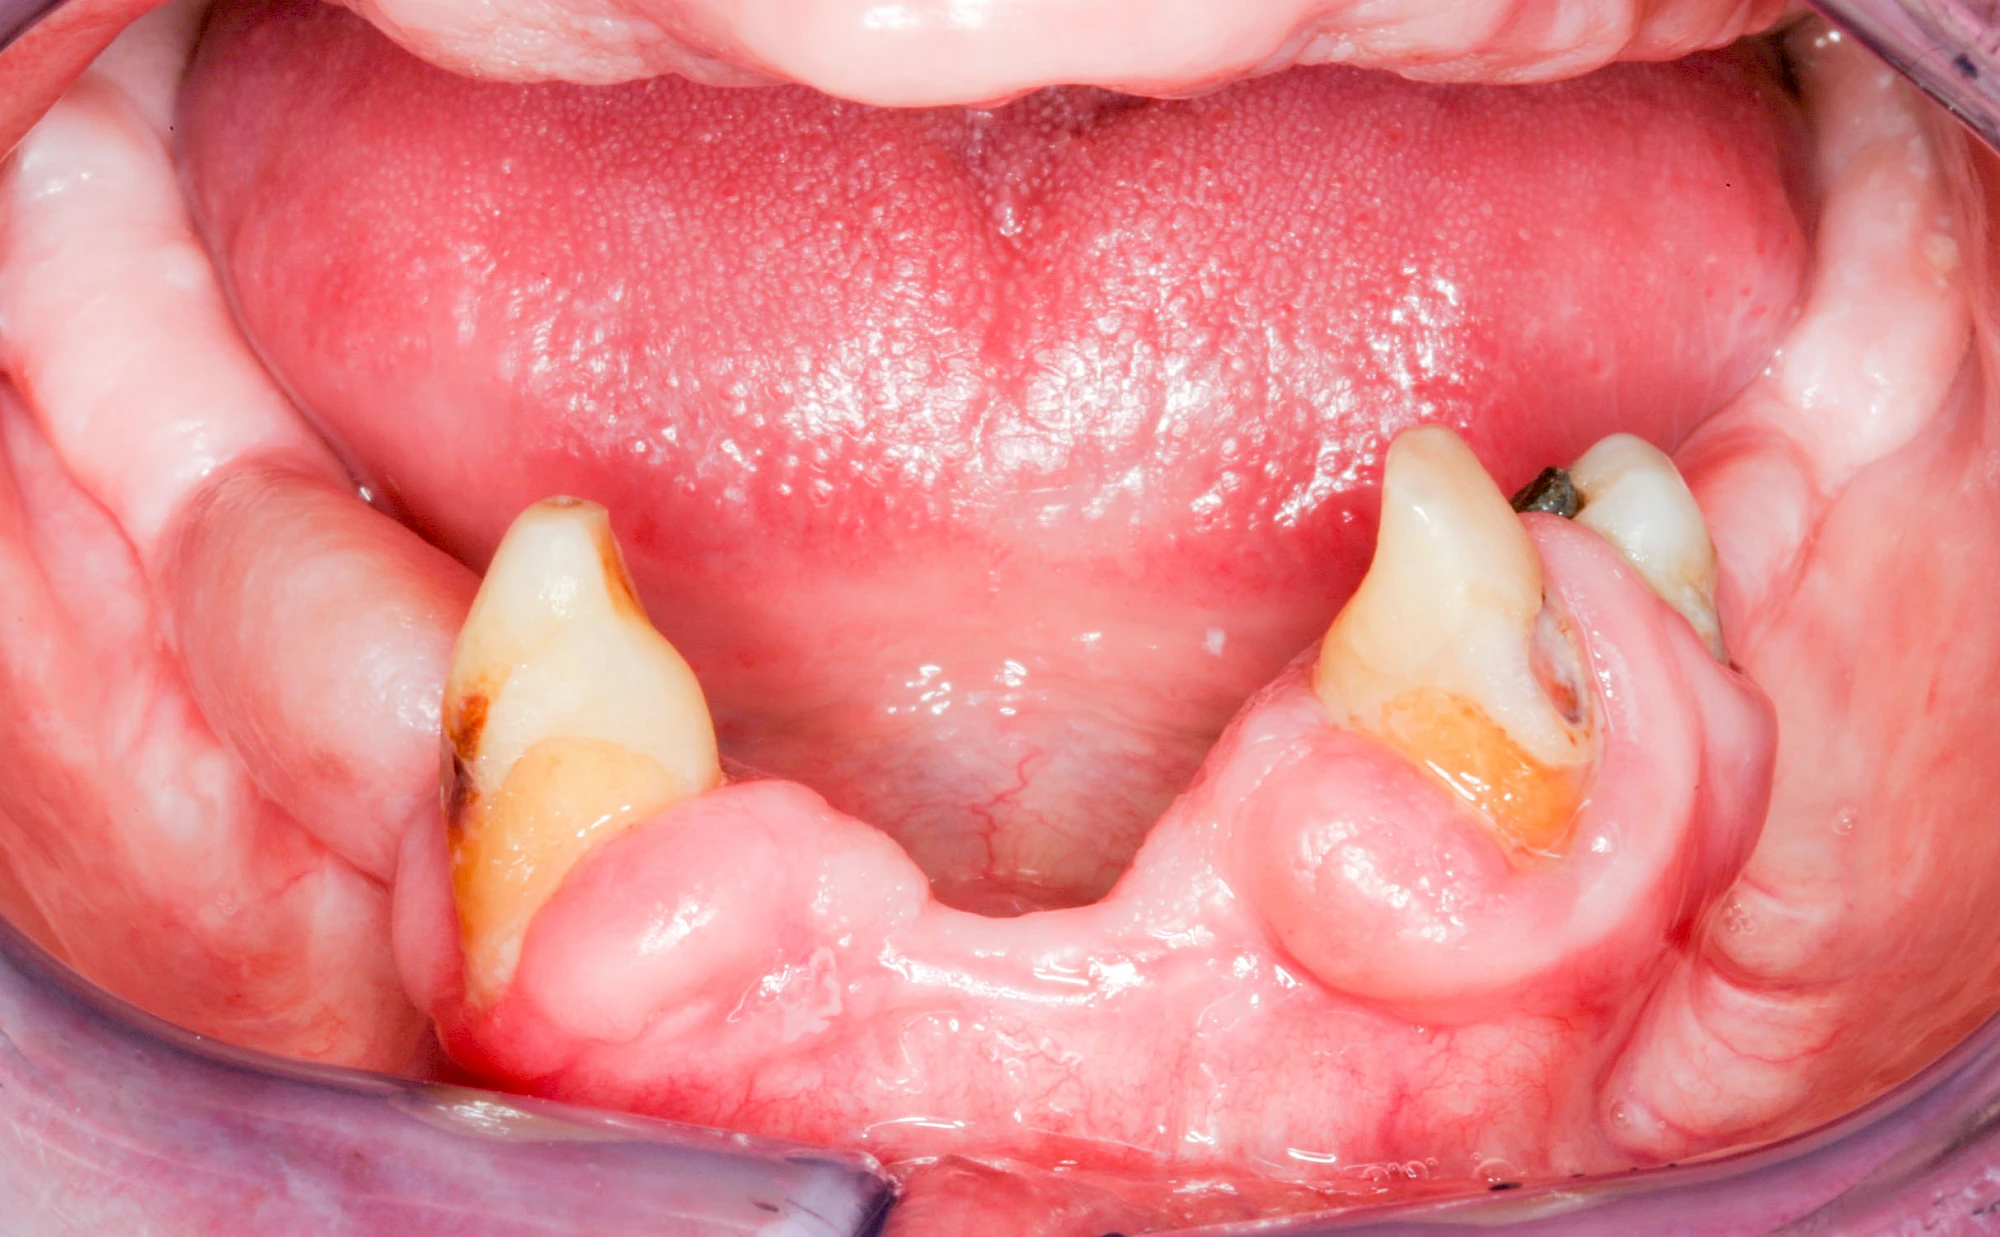

Ist zunächst nur das Zahnfleisch von der Entzündung betroffen, spricht man von Gingivitis. Später, wenn auch der Knochen um die Zähne herum entzündet ist, spricht man von einer Parodontitis. Bei der Parodontitis wird der Knochen nach und nach abgebaut und das Zahnfleisch zieht sich zurück. Die Zahnhälse und Zahnwurzeloberflächen liegen mehr und mehr frei. Die Zähne werden zunehmend lockerer und fallen schließlich aus.